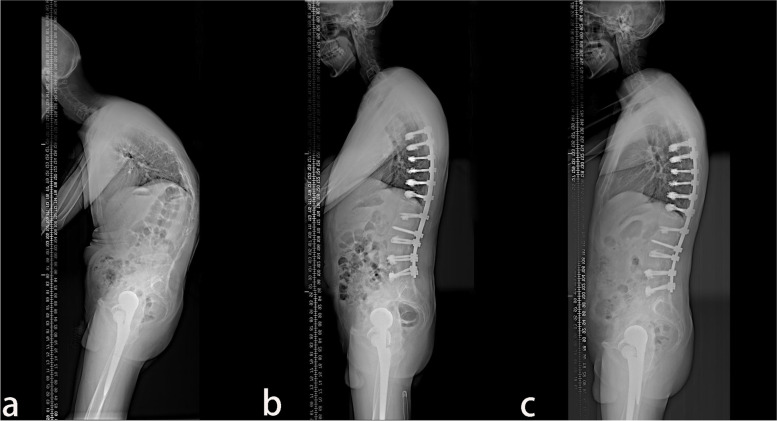

A total of 38 patients with AS combined with thoracolumbar kyphosis were successfully treated by PSO, with a mean follow-up time of 26.9 ± 11.9 months. There were 30 males and 8 females with a mean age of 41.6 ± 7.1 years. Twenty patients consisted in the lumbar lordosis group and 18 patients in the lumbar kyphosis group, with a mean operation time of 289.4 ± 123.2 min and 267.8 ± 96.8 min (P > 0.05), respectively. The patients were further subdivided into the lumbar lordosis T12 group (Fig. 1) with 11 patients, the lumbar lordosis L1 group (Fig. 2) with 9 patients, the lumbar kyphosis L2 group (Fig. 3) with 10 patients, and the lumbar kyphosis L3 group (Fig. 4) with 8 patients.

Fig. 1.

A 31-year old male with AS. a The preoperative X-ray showed that the parietal vertebrae were located at L1, which belonged to the lumbar lordosis group. b) Single-segment pedicle subtraction osteotomy (PSO) was conducted at T12. Lumbar lordosis, global kyphosis, and sagittal vertical axis improved from the preoperative –44°, 86°, and 162.29 mm to –45°, 47°, and 24.41 mm, respectively. c) At the last follow-up in the 16th-month post-operation, no apparent orthopedic loss was observed, and lumbar lordosis, global kyphosis, and sagittal vertical axis were –41°, 53°, and 30.67 mm, respectively